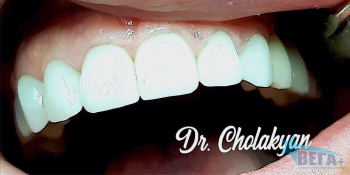

Примеры работ

Стоматологи, оказывающие услугу Установка виниров